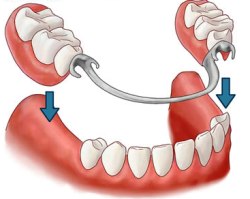

Prótese Dentária Removível (Acrílica, Esquelética e Flexível)

Prótese Removível é a área da Medicina Dentária que tem por objectivo a reabilitação de dentes perdidos através da utilização de um "aparelho removível" que substitui os dentes naturais perdidos. Este tratamento é a alternativa mais económica na reabilitação oral. As Próteses têm como fundamento a reposição das peças dentárias perdidas, para que a pessoa possa voltar a comer, mastigar e realizar as suas funções normais, recuperando a harmonia e beleza facial e rejuvenescendo a aparência. As Próteses Removíveis podem ser Totais - quando substituem todos os dentes de um maxilar; Parciais - quando substituem apenas alguns dentes ausentes; Quanto aos materiais utilizados podem ser Acrílicas (em resina acrílica), ou em Metal (cromocobalto ou esqueléticas). Existe ainda em alguns casos indicação para Próteses Flexíveis.